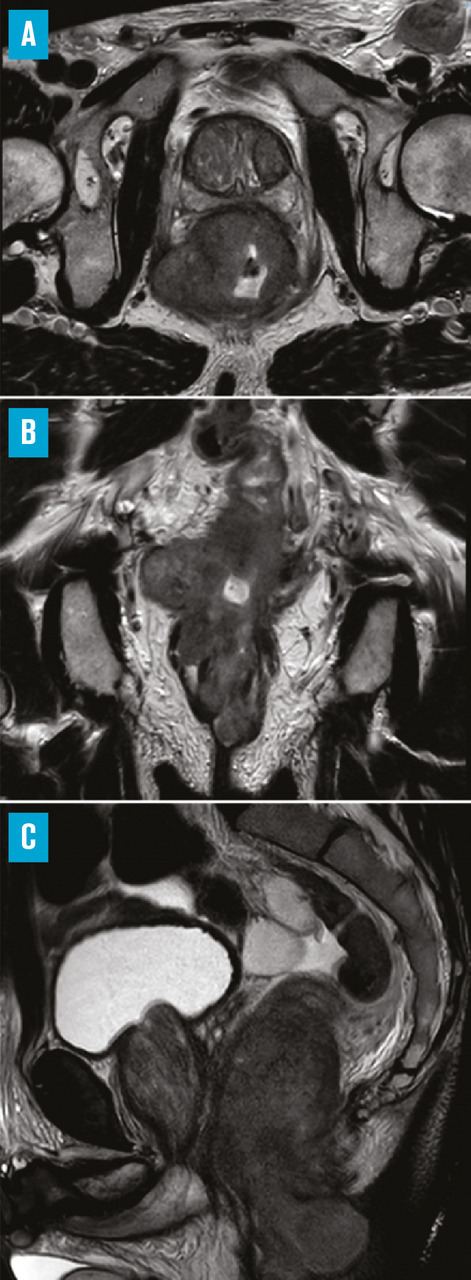

Pour l’extension locale, l’IRM pelvienne est le meilleur examen

Elle évalue la taille et la localisation de la tumeur anale, ainsi que l’envahissement d’un organe de voisinage ou de la cloison rectovaginale. Elle peut également révéler des adénopathies mésorectales, inguinales, iliaques internes ou externes (fig. 1). Elle peut être fusionnée avec le scanner de centrage, pour aider à déterminer les volumes à irradier par le radiothérapeute.